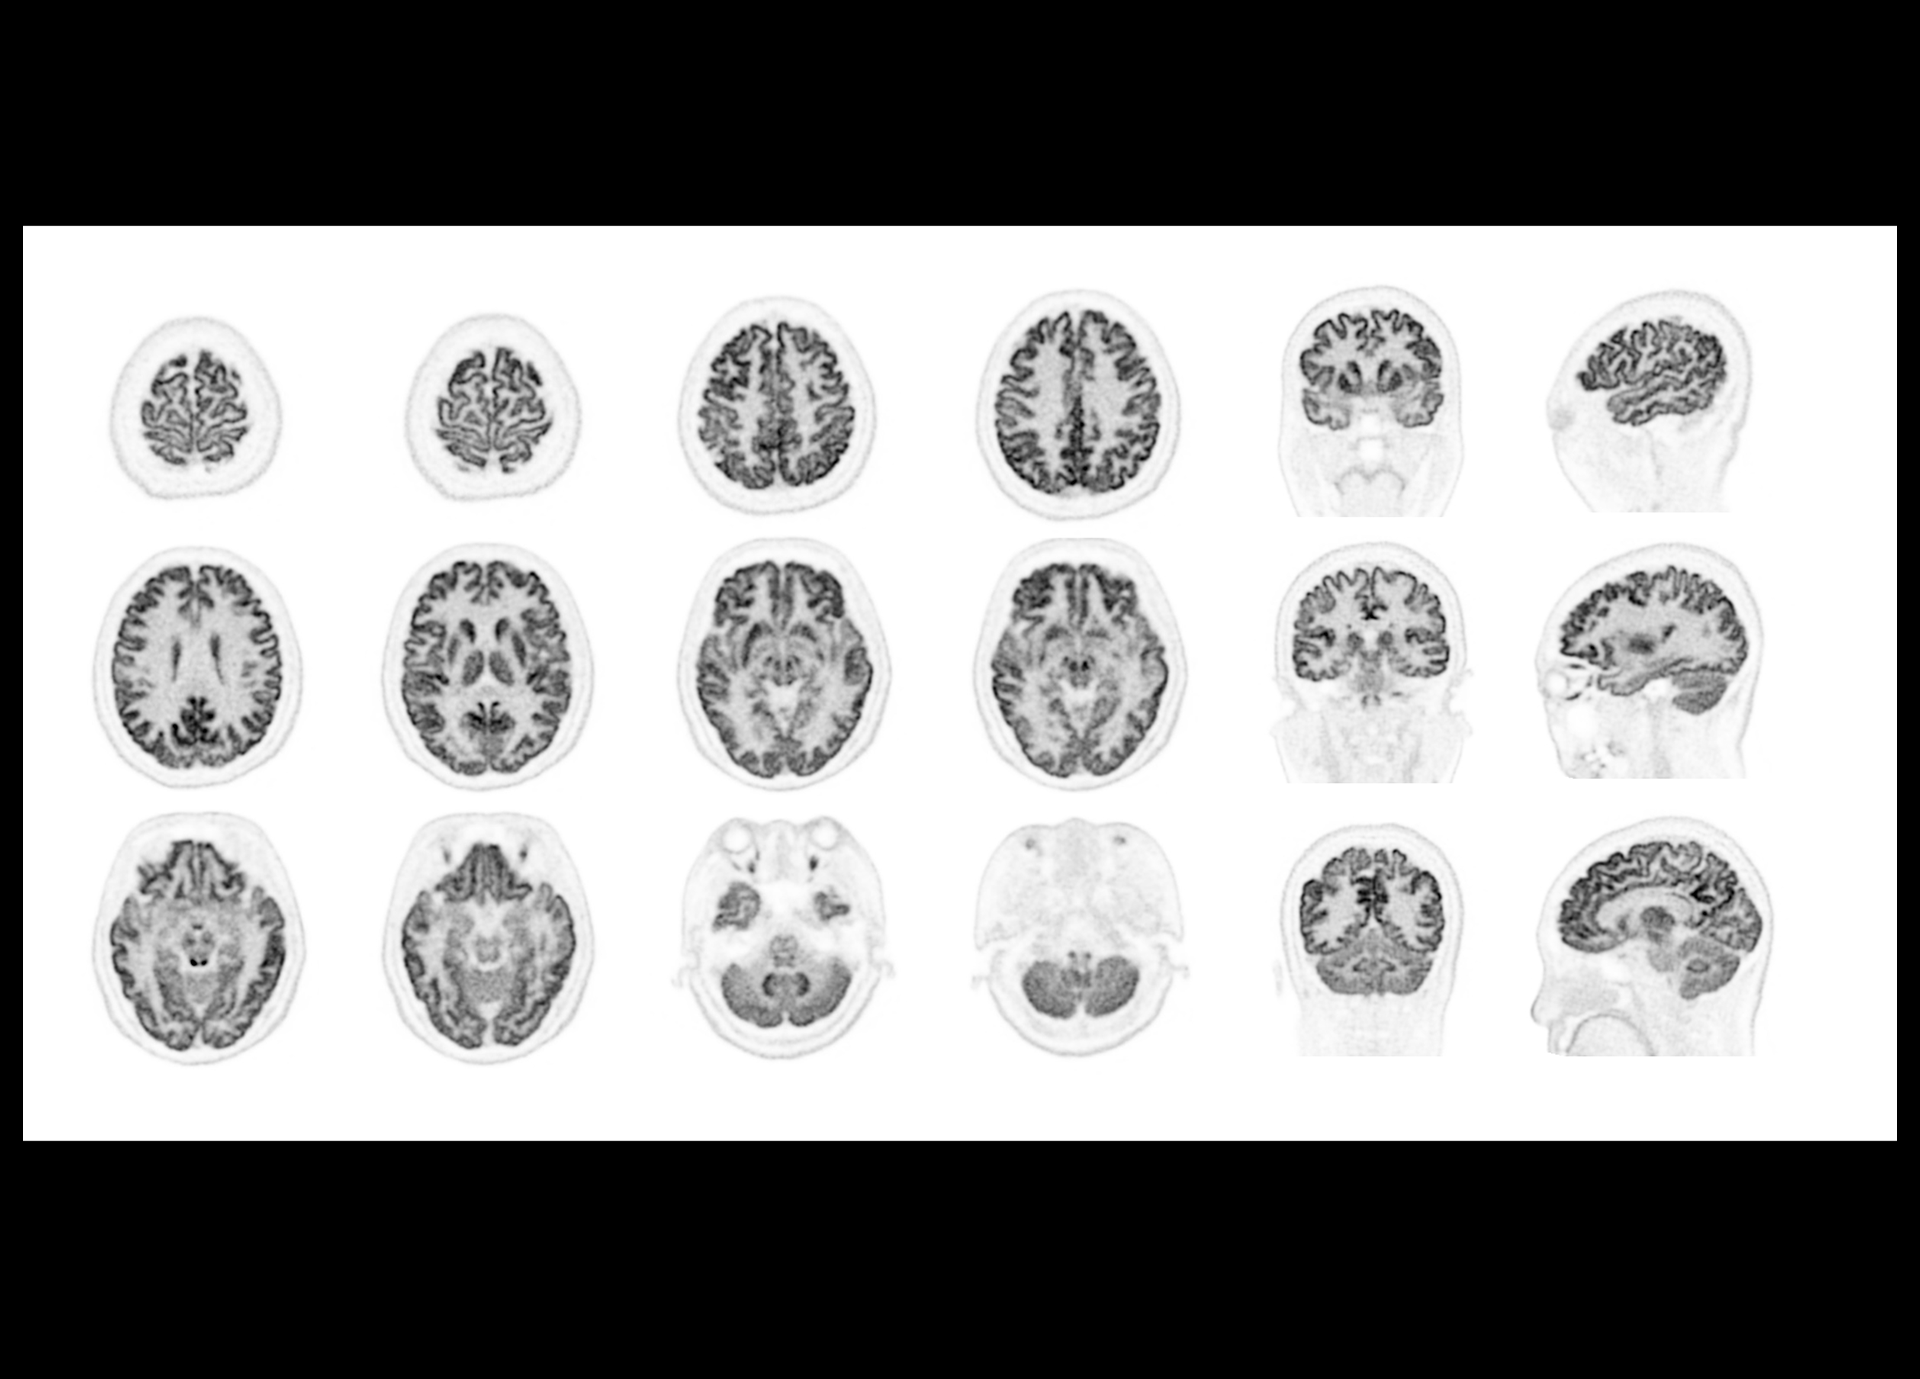

Exceptional NEMA spatial resolution delivered by the finest crystal size of 2.76 mm in the industry.